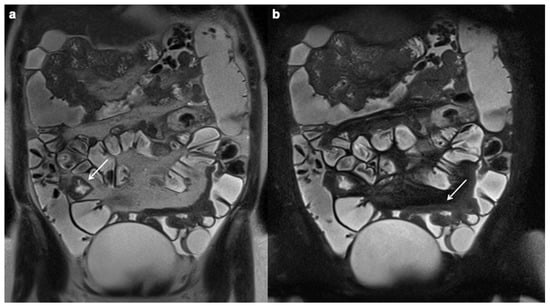

- Church, P.C.; Turner, D.; Feldman, B.M.; Walters, T.D.; Greer, M.-L.; Amitai, M.M.; Griffiths, A.M.; the ImageKids study group. Systematic review with meta-analysis: Magnetic resonance enterography signs for the detection of inflammation and intestinal damage in Crohn’s disease. Aliment. Pharmacol. Ther. 2014, 41, 153–166. [Google Scholar] [CrossRef]

- Tolan, D.J.M.; Greenhalgh, R.; Zealley, I.A.; Halligan, S.; Taylor, S.A. MR Enterographic Manifestations of Small Bowel Crohn Disease. RadioGraphics 2010, 30, 367–384. [Google Scholar] [CrossRef] [Green Version]

- Steward, M.J.; Punwani, S.; Proctor, I.; Adjei-Gyamfi, Y.; Chatterjee, F.; Bloom, S.; Novelli, M.; Halligan, S.; Rodriguez-Justo, M.; Taylor, S. Non-perforating small bowel Crohn’s disease assessed by MRI enterography: Derivation and histopathological validation of an MR-based activity index. Eur. J. Radiol. 2012, 81, 2080–2088. [Google Scholar] [CrossRef]

- Rimola, J.; Ordás, I.; Rodriguez, S. Magnetic resonance imaging for evaluation of Crohn’s disease: Validation of parameters of severity and quantitative index of activity. Inflamm. Bowel Dis. 2011, 17, 1759–1768. [Google Scholar] [CrossRef]

Wall thickening

| Intramural edema |

| Stricture |

| Ulcerations |

| Perienteric edema and/or inflammation |

| Engorged vasa recta |